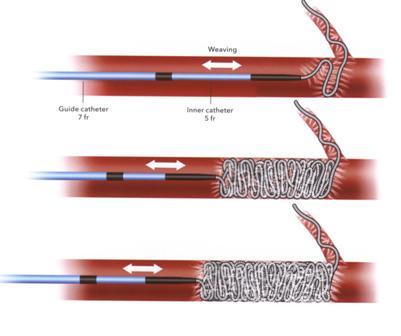

技术之二,锚定和脚手架技术:主要用于大动脉阻塞,将弹簧栓子部分锚定在血管的某一分支上。弹簧栓子的直径>血管直径。往复推送弹簧栓子(go to and fro and push)

脚手架技术(Scaffold technique)

|

选用较大的弹簧栓子,利用高径向支撑力。可推式弹簧栓子的脚手架(Scaffold)技术。先非致密性阻塞血管,再将推送管重新推回起始点在释放弹簧栓子。 |